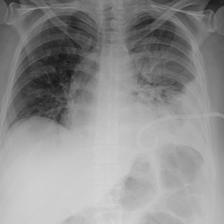

Table A.1 shows example reports generated with BioViL-T and BioViL models, which are compared to the reference radiologist’s reports. In comparison with BioViL which only models the current image, BioViL-T shows the benefit from incorporating prior study information and is able to provide factually more accurate reports especially in terms of describing temporal progression of the findings. This is showcased in the first two examples in the table: In the first row, BioViL-T is able to comment on not only the presence of the pleural effusion but also its improvement while BioViL fails to mention the change. In the second example, BioViL-T is able to correctly identify that there is no relevant change by comparing with the previous study, while BioViL wrongly hallucinates the tube in the current image as a new placement. BioViL-T can also avoid hallucination of the temporal information when there is no prior study. For instance, in the third example, BioViL-T correctly acknowledges that there is no prior image and generates the report based on information from the single current image, while BioViL hallucinates a non-exisistent prior study and wrongly generates temporal descriptions in the report.

| Reference (by radiologist) | BioViL | BioViL-T |

|---|---|---|

| No evidence of acute cardiopulmonary process. Decreased right pleural effusion. | Small right pleural effusion. | Small right pleural effusion, decreased since _. |

| No relevant change as compared to the previous image. No evidence of pneumonia or other parenchymal pathology. Normal size of the heart. No pleural effusions. | In comparison with the study of _, there has been placement of a right ij port - a - cath that extends to the lower svc. No evidence of post procedure pneumothorax. The cardiac silhouette is within normal limits and there is no vascular congestion or pleural effusion. There is some asymmetry of opacification at the bases, more prominent on the left. In the appropriate clinical setting, this could possibly represent a developing consolidation. | As compared to the previous radiograph, no relevant change is seen. The lung volumes are normal. Normal size of the cardiac silhouette. Normal hilar and mediastinal structures. No pneumonia, no pulmonary edema, no pleural effusions. |

| No previous images. The cardiac silhouette is within normal limits and there is no evidence of vascular congestion, pleural effusion, or acute focal pneumonia. | In comparison with the study of _, there is little change and no evidence of acute cardiopulmonary disease. No pneumonia, vascular congestion, or pleural effusion. | No previous images. The cardiac silhouette is within normal limits and there is no vascular congestion, pleural effusion, or acute focal pneumonia. |